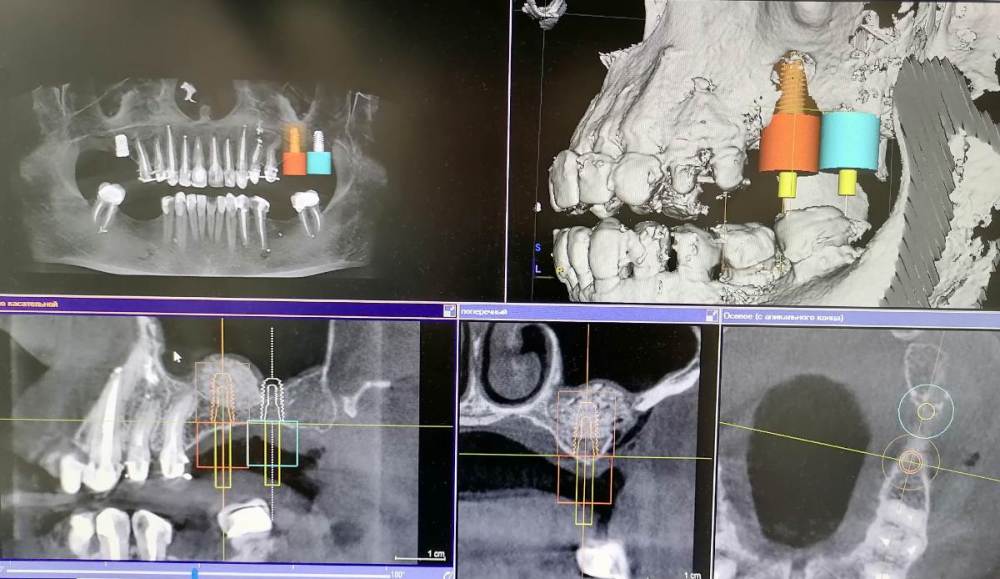

Ponchik Опубликовано 26 марта, 2021 Поделиться Опубликовано 26 марта, 2021 Планировалось: удаление 2.5 зуба, синуслифтинг и вторым заходом имплантация 2.6, 2.7 Получилось: ортопед решил оставить 2.5, одел временную. Хирург (я) решил, что от кривулины 2.5 он будет при имплантации убегать и т.д. и поставит имплантант в области 2.6 (ближе к 2.7) ну и соответственно 3.7 парой бугров какой-то контакт себе найдёт и будет всем счастье. И сделал синуслифтинг для 2.6. Оказалось, что ортопед таки всё ещё хочет имплантант в позиции 2.7. Зря я поумничал. Теперь думаю в какие сроки делать окно в области 2.7? Ждать полгода? ПыСы : В области 1.6 имплантант ставил лет 5-7 назад кто-то, где-то. Он в кости на 3-4мм. Надо будет убрать, но пока не про это. Скрытый текст Ссылка на комментарий

Ponchik Опубликовано 26 марта, 2021 Автор Поделиться Опубликовано 26 марта, 2021 2 часа назад, АнтонТЛТ сказал: Какой размер планируется в области 27? Думаю без фанатизма - 4.5-10 (4.5-8 если пробовать закрытый) Ссылка на комментарий